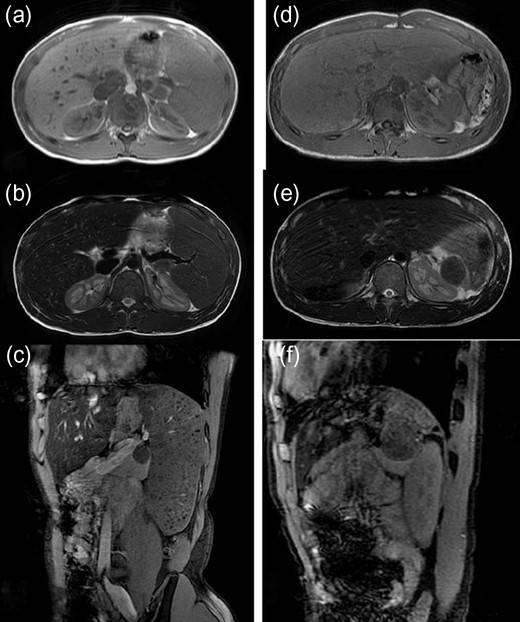

A 16-year-old boy was admitted with a rapidly growing pancreatic mass. He had received a diagnosis of HS based on the following: the need for a blood transfusion to treat anemia after birth, a history of hemolytic anemia, and a family history of HS. He had often undergone medical examinations for anemia and jaundice in junior and senior high school. When he was 15 years old, he visited our hospital because of the rapid onset of jaundice. Radiological examinations, such as computed tomography (CT) (Fig. 1a–c) and magnetic resonance imaging (MRI) (Fig. 2a–c), showed a huge spleen and a 2-cm mass near or in the pancreatic tail. Sonazoid-enhanced ultrasonography showed hypervascularity in the mass, which appeared to be located near the pancreatic tail and raised suspicions about an accessory spleen (Fig. 3a). The patient underwent a successful splenectomy by laparotomy, but the mass found on the preoperative examination could not be found by inspection and intraoperative ultrasonography (Fig. 4a and b). The mass grew rapidly to 4 cm one year after splenectomy, as shown on the radiological examinations (Figs 1d–f, 2d–f and 3b), but a recurrence of HS with anemia or jaundice did not develop. However, he underwent successful laparoscopic surgery to aid in the differential diagnosis. After the adhesions of the omentum to the abdominal wall were detached, the laparoscopic ultrasonogram revealed the mass in the pancreatic tail. He underwent laparoscopic distal pancreatectomy (Fig. 4c and d), and he had no clinical symptoms or signs of local infection or sepsis. A CT on the ninth postoperative day showed a small peripancreatic collection (Grade B: the clinical grading of postoperative pancreatic fistula). He was discharged on the 11th postoperative day. The resected specimen revealed the intrapancreatic mass that was covered with pancreatic tissues, and the intrapancreatic mass was an accessory spleen (Fig. 4e).

Magnetic resonance imaging (MRI) (before and after splenectomy). (a–c) Before splenectomy: MRI shows a huge spleen and a 2-cm mass in the pancreatic tail. (d–f) After splenectomy: MRI shows the mass in the pancreatic tail grows rapidly to 4 cm.

In the present case, the preoperative enhanced and plain CTs could not differentiate the location of the mass as being in the pancreas or near the pancreas, but an MRI revealed the intrapancreatic mass. On the other hand, contrast-enhanced ultrasound could detect the characteristic features of the mass. From these findings, it is clear that an MRI and contrast-enhanced ultrasound are useful to diagnose the IPAS.